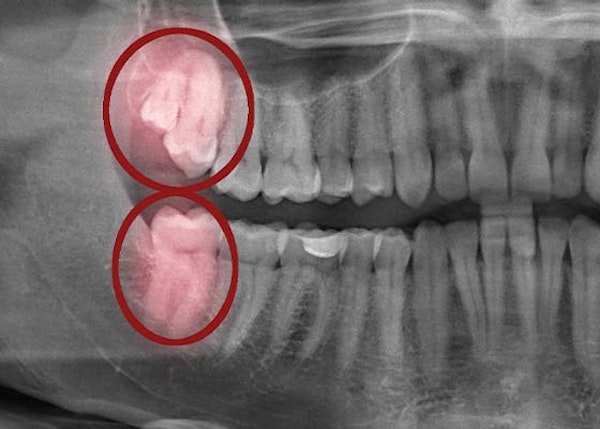

Don't wait until the pain from impacted wisdom teeth sends you to our Vancouver dentist's office. Come in for regular appointments ahead of time to get X-rays and a close-up view of how your wisdom teeth are growing. That way, we can help prevent pain and problems before they start.

CT scans give our dentists a closer look at the visible parts of your teeth as well as the tooth roots, blood vessels, soft tissues, and other parts of the mouth that the eye can't see. These scans give us a more detailed view of the position of your wisdom teeth when they haven't yet erupted. We can also take digital impressions of your teeth using our intraoral scanner. We aim to give you an accurate view of your smile and improve your overall wellness by using this technology and other advanced tools at our Vancouver dental office.

This is why visiting your dentist regularly is so important. They can use X-rays to watch as your teeth emerge and determine if they'll be a problem in the future or if they can stay.